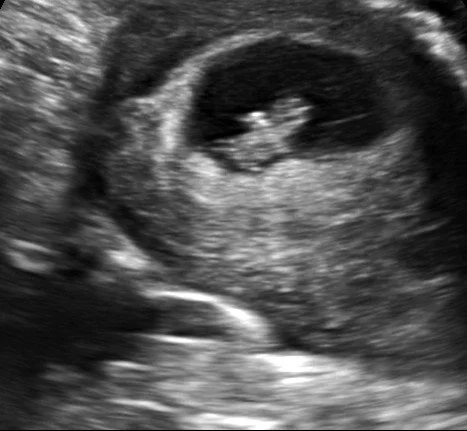

2D First Womb Date

Recommended to come in 8+ weeks on as we offer abdominal ultrasounds and baby can be seen easier around 8 weeks onward, remember we are looking for a baby the size of a raspberry at 8 weeks. The First Womb Date makes for the perfect opportunity to get those pregnancy announcement sonogram pictures! Or if you just want to peek at your baby!

Starting at 8-14+ weeks in pregnancy!